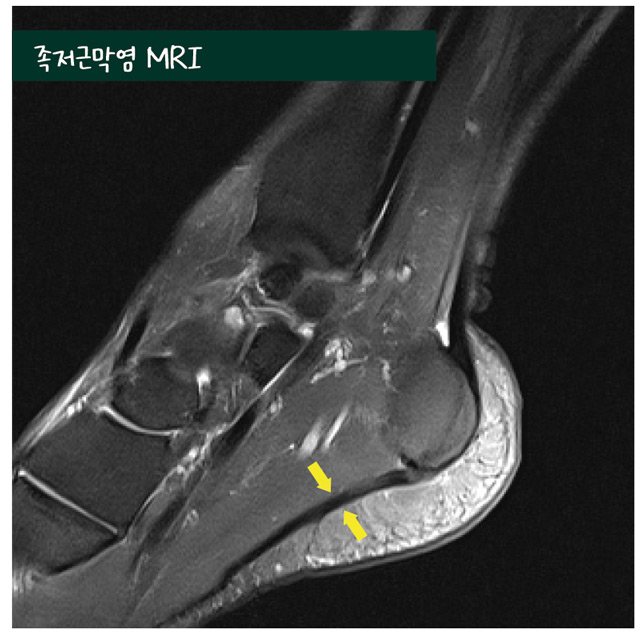

진찰 시에는 발 뒤꿈치 뼈 전내측 종 골 결절 부위에 압통이 있고, 족저근막을 따라 발바닥 에 전반적인 통증을 보일 수 있습니다. 다른 질 환과의 감별진단을 위하여 방사선 검사, 초음 파 검사 및 자기공명영상(MRI) 검사를 시행할 수 있습니다.